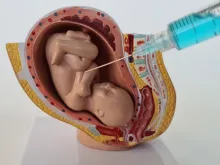

Projeto de Lei propõe proibir cloreto de potássio em abortos tardios previstos em lei

Tramita na Câmara do Deputados um projeto de lei que veta o procedimento de assistolia fetal em casos de aborto... Leia mais

CFM tem que explicar à Justiça resolução que proíbe uso de cloreto de potássio em abortos

Ontem (8), a Justiça Federal de Porto Alegre deu prazo de 72 horas para o Conselho Federal de Medicina (CFM)... Leia mais

PSOL quer suspender resolução do CFM que proíbe uso de cloreto de potássio em abortos tardios

Líder da federação PSOL-Rede na Câmara dos Deputados, Erika Hilton (PSOL-SP), parlamentar que se identifica como mulher, apresentou ontem (4),... Leia mais

Conselho Federal de Medicina proíbe droga usada em aborto legal depois da 22ª semana

O Conselho Federal de Medicina (CFM) publicou na última quinta-feira (21), uma resolução que proíbe o uso de cloreto de... Leia mais